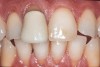

Figure 9  Preoperative photograph of a case requiring significant lengthening. There is at least medium risk of flexure and unfavorable stress, and some of the substrate would be dentin. Thus, Category 1 materials were eliminated as a choice.

Figure 9

Figure 10  Postoperative photograph after Category 2 materials were applied, with minimal porcelain layering in the incisal one third.

Figure 10